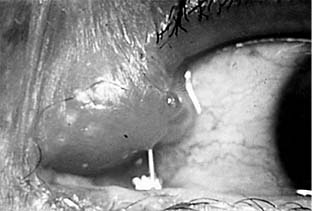

Figure 4-14

Figure 4-14: Acute dacryocystitis.